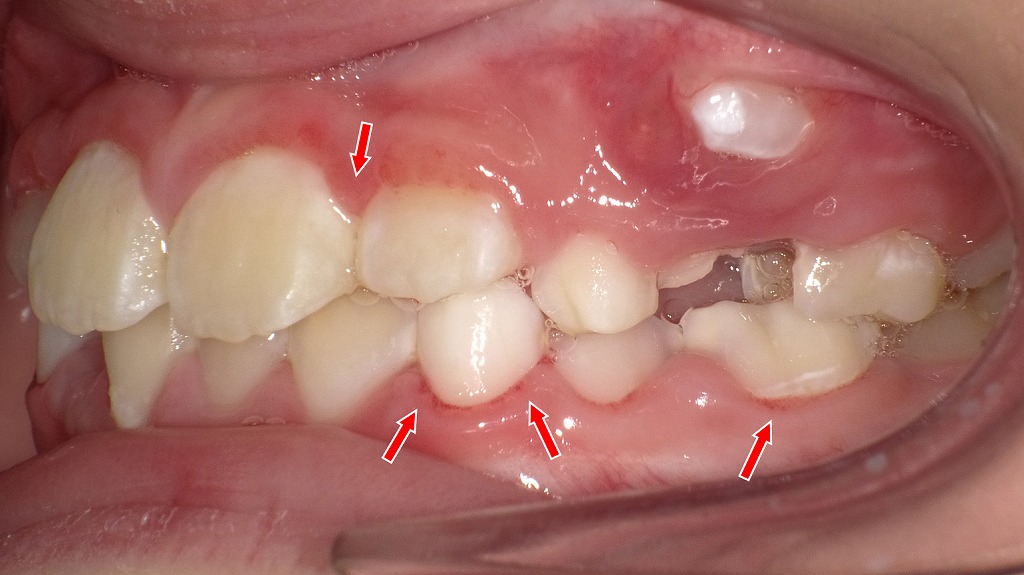

赤い矢印の部分に歯ぐきの腫れ・赤み・プラークの付着・出血しやすい部位が示されています。これは典型的な**子どもの歯肉炎(子ども特有の歯ぐきの炎症)**の特徴です。

🖼 画像②(左側面):

■ 生え変わりの影響で磨きにくく、炎症が広がっている

矢印部分は、前歯から乳臼歯にかけて歯ぐきがぷっくり腫れた状態です。

生えかけの永久歯の周りは段差が大きく、磨き残しが非常に多い場所です。

■ 奥歯にもプラーク付着

生えかけの永久歯が歯茎の高い位置にあり、

歯ぐきの赤みが強く、炎症が波及しています。